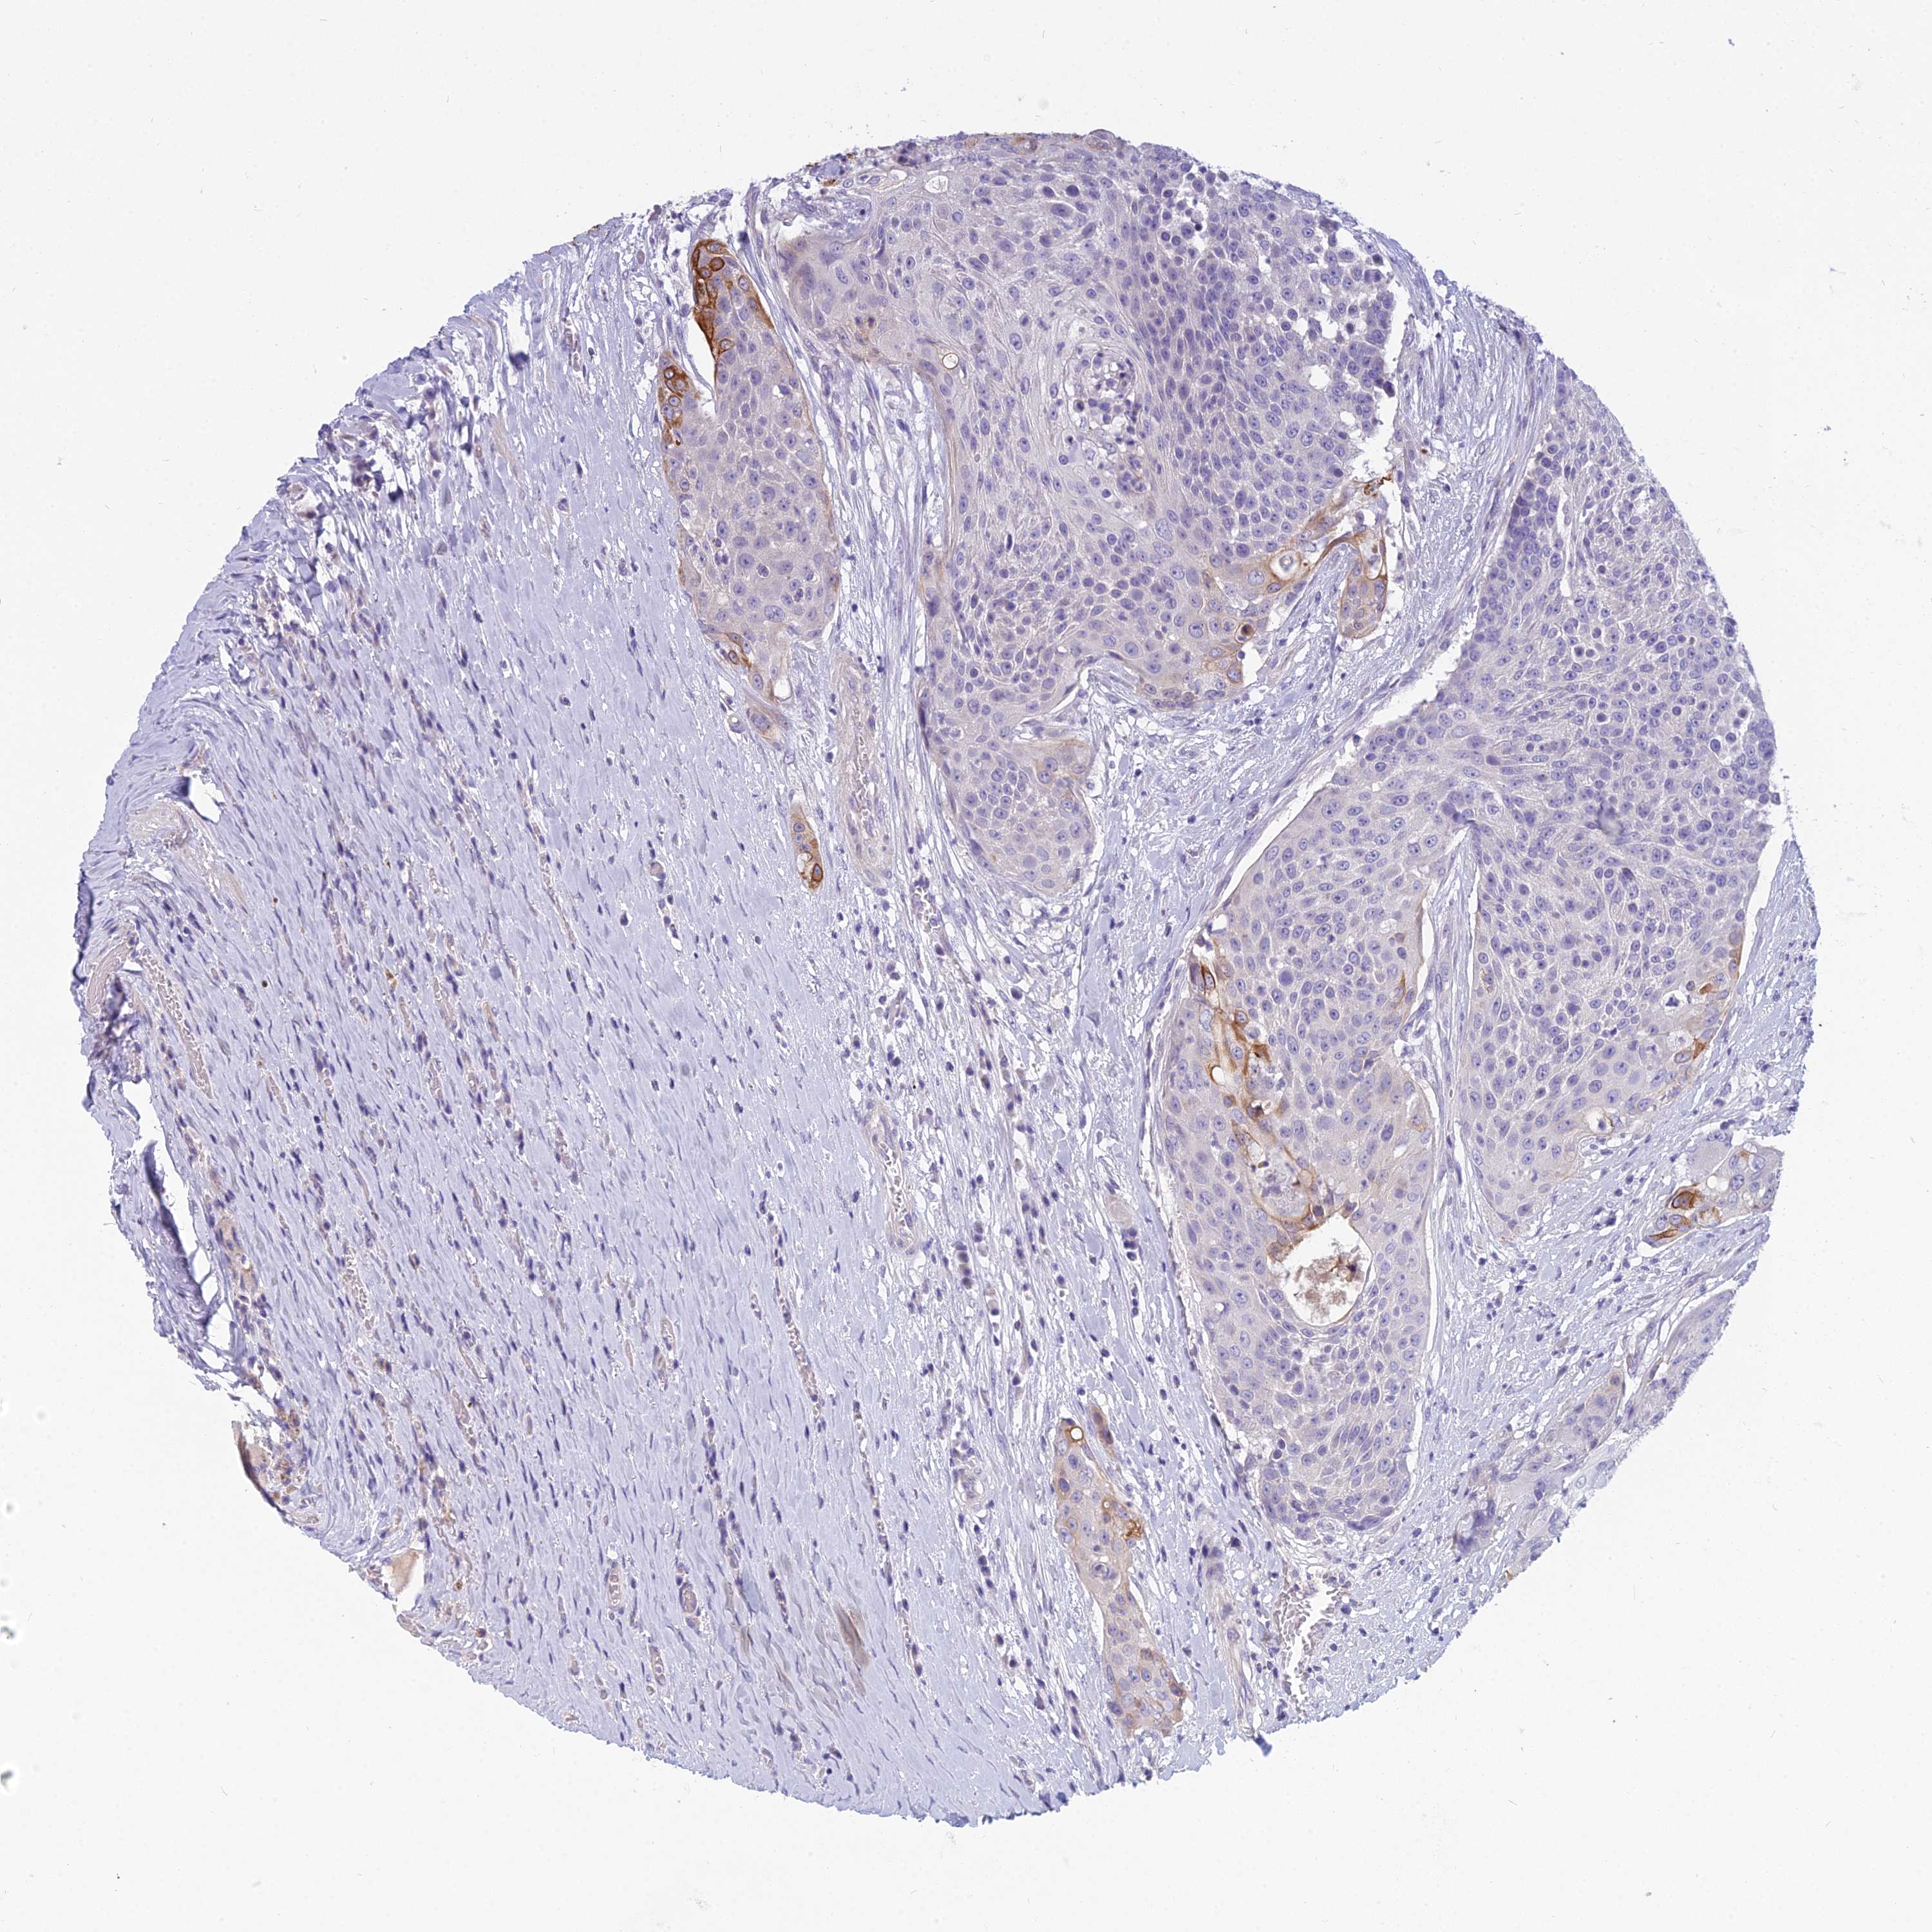

UROTHELIAL CANCER - Protein expressioni

A mouse-over function shows sample information and annotation data. Click on an image to view it in a full screen mode. Samples can be filtered based on level of antibody staining by selecting one or several of the following categories: high, medium, low and not detected. The assay and annotation is described here.

Note that samples used for immunohistochemistry by the Human Protein Atlas do not correspond to samples in the TCGA dataset.

Antibody stainingi

Antibody staining in the annotated cell types in the current human tissue is reported as not detected, low, medium, or high, based on conventional immunohistochemistry profiling in selected tissues. This score is based on the combination of the staining intensity and fraction of stained cells.

Each image is clickable and will lead to virtual microscopy that enables deeper exploration of all samples and also displays staining intensity scores, fraction scores and subcellular localization as well as patient and tissue information for each sample.

Antibody HPA042881

Staining

High

Medium

Low

Not detected

Intensity

Strong

Moderate

Weak

Negative

Quantity

>75%

75%-25%

<25%

None

Location

Nuclear

Cytoplasmic/membranous

Cytoplasmic/membranous,nuclear

Urothelial carcinoma, High grade

Urothelial carcinoma, Low grade